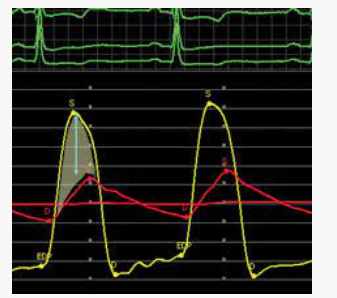

What is being observed a systolic or diastolic gradient

A diastolic gradient is being observed due to the pressure difference between the left atrium and left ventricle during diastole.

Ao stenosis waveform

what gradient can be observed in severe aortic stenosis

SYSTOLIC LV/AO gradient

in mitral stenosis a ****** gradient is observed between

diastolic gradient

LV and LA